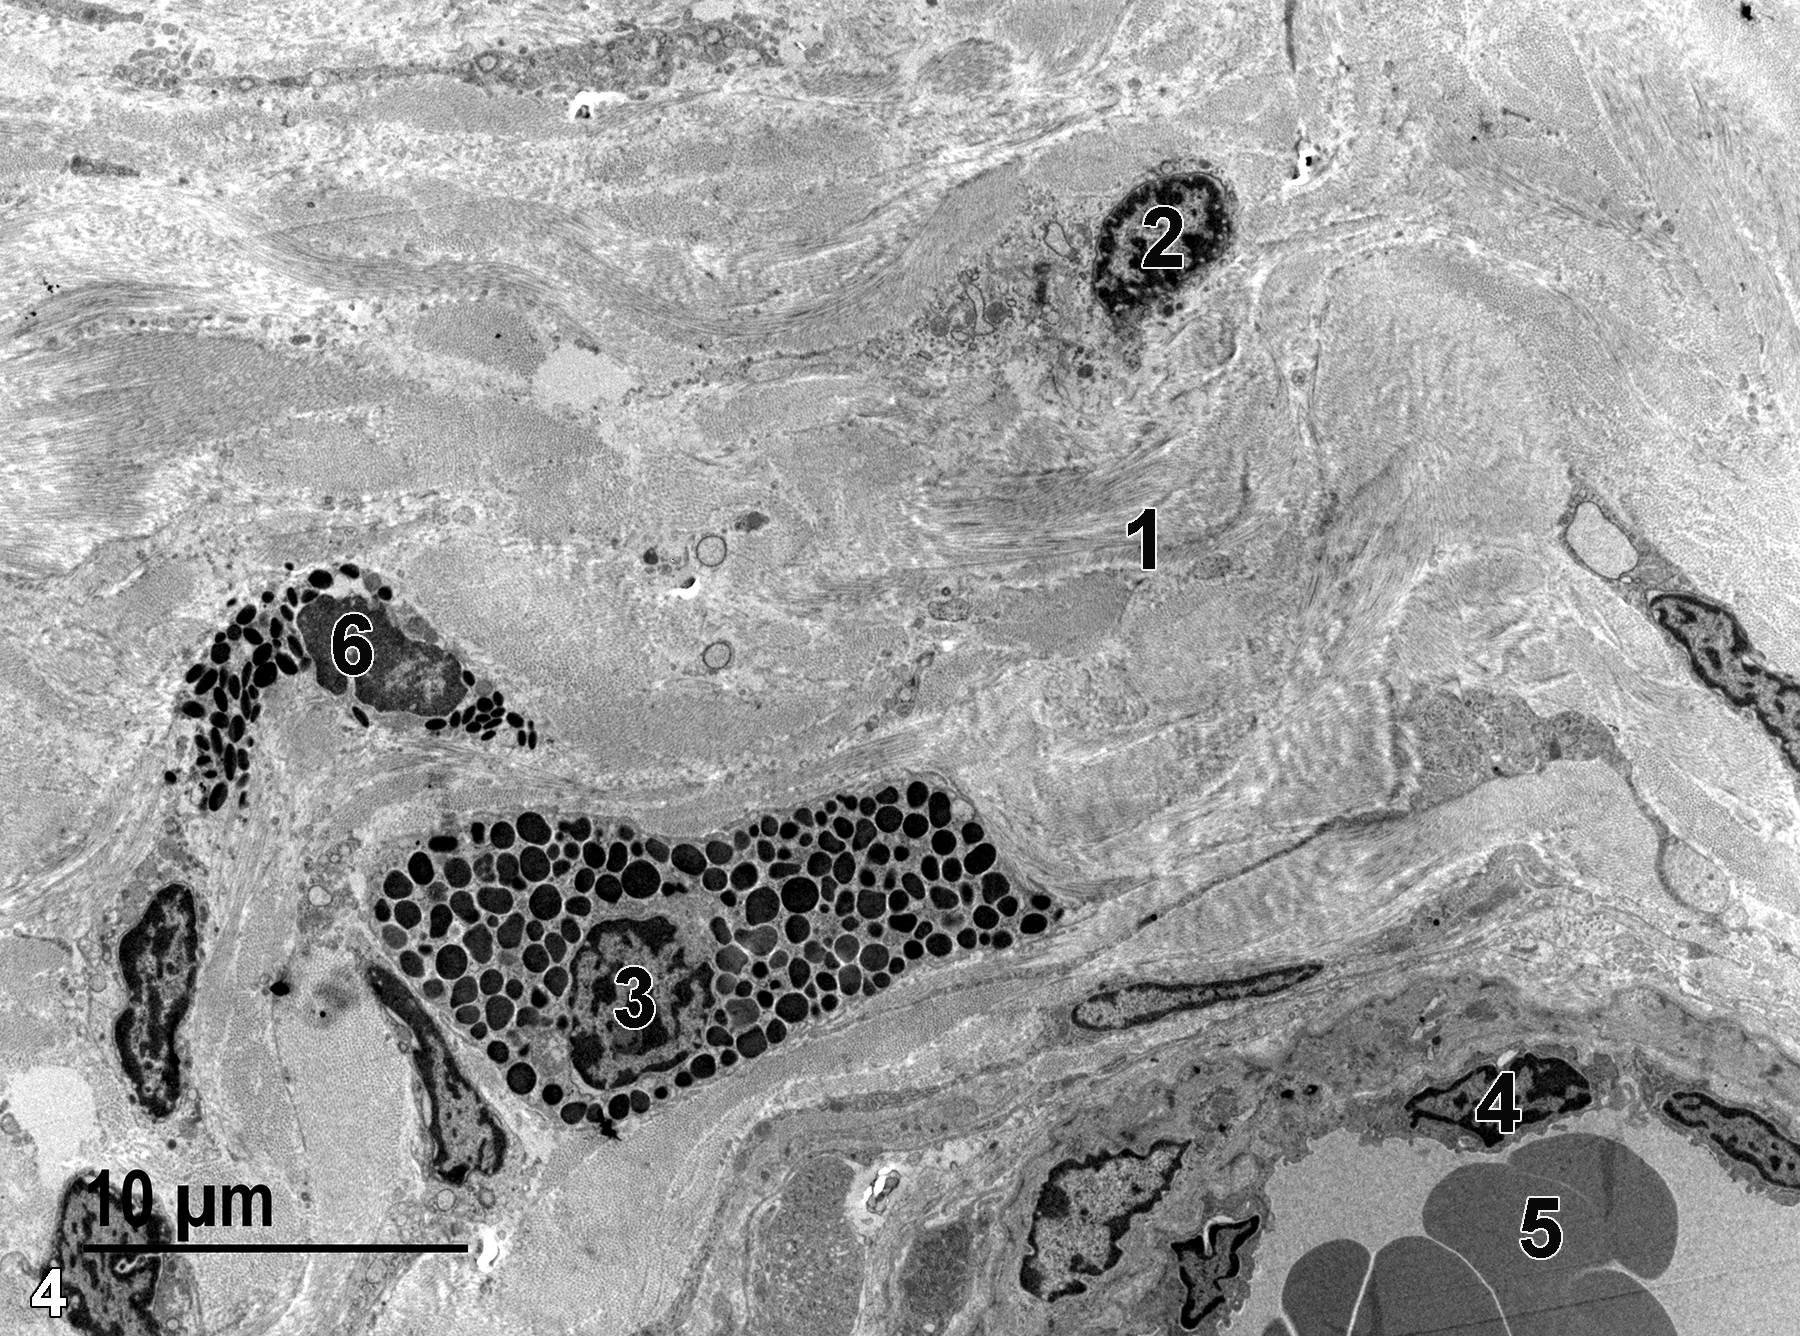

The vagina is a tubular organ lined with a vaginal wall with a well-vascularized mucous membrane that consists of a stratified epithelial cell layer, an intermediate epithelial cell layer, and a layer of basal epithelial cells. The vaginal epithelium undergoes changes depending on the stage of the estrous cycle observed (Dixon et al. 2018). The epithelial cells contain numerous tonofilaments and desmosomes that connect cellular projections into the intercellular spaces. Mitochondria, glycogen, and ribosomes are present. Below the epithelium is the lamina propria, which consists of collagenous connective tissue with fibroblasts, neutrophils, eosinophils, and mast cells. Below the lamina propria is a muscularis layer that consists of smooth muscle cells. The outermost layer of the vagina is the adventitia (Young and Heath 2000).